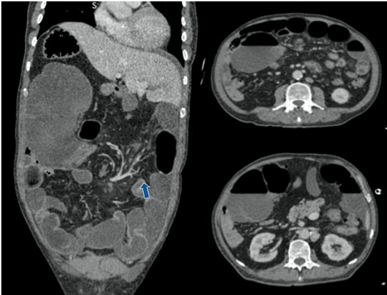

Se trata de un varón de 72 años, con antecedente de prostatectomía radical en 2019 por carcinoma de próstata, complicada con perforación iatrogénica de recto que requirió colostomía, con posterior reconstrucción del tránsito en un segundo tiempo quirúrgico. Se encontraba recibiendo radioterapia por recaída, cuando acude a urgencias por presentar dolor abdominal intenso, localizado en fosa iliaca derecha, asociado a cese de expulsión de heces y gases. Durante el examen físico al momento del ingreso el paciente se encontraba hemodinámicamente normal y estable, afebril, con abdomen distendido y timpánico, doloroso a la palpación profunda en hemiabdomen derecho. En el tacto rectal presentaba la ampolla rectal vacía. Se completó el estudio mediante analítica e imágenes diagnósticas, a saber: radiografía de tórax, que mostró ubicación cardíaca habitual con una discreta cardiomegalia, radiografía de abdomen, en la que se observaba marcada dilatación del marco cólico con ausencia de gas en ampolla rectal en relación con obstrucción intestinal (Figura 1), y tomografía (TC) abdominal, donde se informó situs inversus, marcada dilatación de ciego en hipocondrio derecho, con ingurgitación de vasos y signo del remolino, acompañado de hallazgos sugestivos de un patrón de oclusión a nivel de íleon distal, junto con líquido libre de localización perihepática, periesplénica y pélvica (Figura 2).

Tras dicha valoración se indicó intervención quirúrgica urgente a través de laparotomía mediana supra-infraumbilical, hallando líquido libre seroso, situs inversus abdominal junto con malrotación intestinal IIIB1 donde el colon estaba situado en el hemiabdomen izquierdo y el intestino delgado en el derecho, acompañado de obstrucción intestinal por vólvulo de ciego sobre el eje de la válvula ileocecal. Al constatarse la viabilidad tisular del ciego, se practicó apendicectomía y cecostomía aspirativa a través de la base apendicular. Se decidió realizar resección ileocecal, ya que el ciego presentaba áreas de deserosamiento, y reconstrucción del tránsito mediante anastomosis ileocólica laterolateral con sutura mecánica (Figura 3).